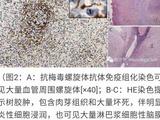

BTRBGD是一种罕见的常染色体隐性遗传病,与定位于染色体2q36.3上的SLC19A3基因突变有关。本病最早在1998年由沙特医生Ozand等报告。SLC19A3基因编码硫胺素转运蛋白-2(THTR2),THTR2是已知的硫胺素转运蛋白之一,主要介导硫胺素在肠道的吸收,硫胺素吸收之后转化为焦磷酸硫胺素,作为几个能量代谢关键酶的必需辅酶,参与到碳水化合物和氨基酸代谢产能的过程中。BTRBGD的发病与硫胺素缺乏导致的能量代谢障碍有关,因相似的临床症状及影像学特征,常被误诊为Leigh综合征。BTRBGD通常在儿童期起病,已报告的最小起病年龄为1月龄。临床过程分为3个阶段,第1阶段为亚急性脑病,常于发热或其他应激状态之后出现呕吐、意识障碍等;第2阶段为急性脑病,表现癫痫发作、锥体束征、锥体外系症状(肌张力障碍、吞咽困难、构音障碍)等;第3阶段为慢性或缓慢进展的脑病,表现缄默木僵状态,彻底丧失语言和理解能力,最终死亡。影像学表现具有特征性,见对称性尾状核、壳核血管源性水肿,还可以累及幕上、幕下皮质和脑干,多数病例在随访中出现基底节区萎缩或坏死。早期的治疗经验为单独给予大剂量生物素,治疗后可以逆转临床症状,但三分之一的患者会复发急性代谢危象。Tabarki等发现生物素和硫胺素联合应用的长期疗效并不优于单用硫氨素治疗,但可以缩短急性危象的恢复时间。仍不清楚为什么硫胺素转运子基因突变会对外源性生物素治疗有反应。当前推荐的治疗方案为生物素1-2mg(kg·d)和硫胺素10-40mg/(kg·d)。BTRBGD的预后取决于治疗的时机,未治疗或延迟治疗者多已死亡或遗留永久的神经功能障碍,在亚急性或急性脑病阶段及时治疗症状可以在数日内恢复,患者维持稳定的代谢状态,部分遗留轻度的神经功能后遗症。本例患儿在予以生物素并增加硫胺素剂量时,已经出现基底节区软化灶及明显神经发育落后,后来又出现了癫痫性痉挛发作,遗留持久的神经功能障碍。BTRBGD作为一种可治疗的代谢性疾病,要早期诊断、早期治疗。SLC19A3基因调控区的变异也可以导致发病,要重视全基因组测序在诊断中的价值。在临床发现儿童原因不明的脑病伴神经影像学显示双侧对称性壳核和尾状核病变,应该及早考虑该病并于基因诊断之前开始生物素和硫胺素治疗。